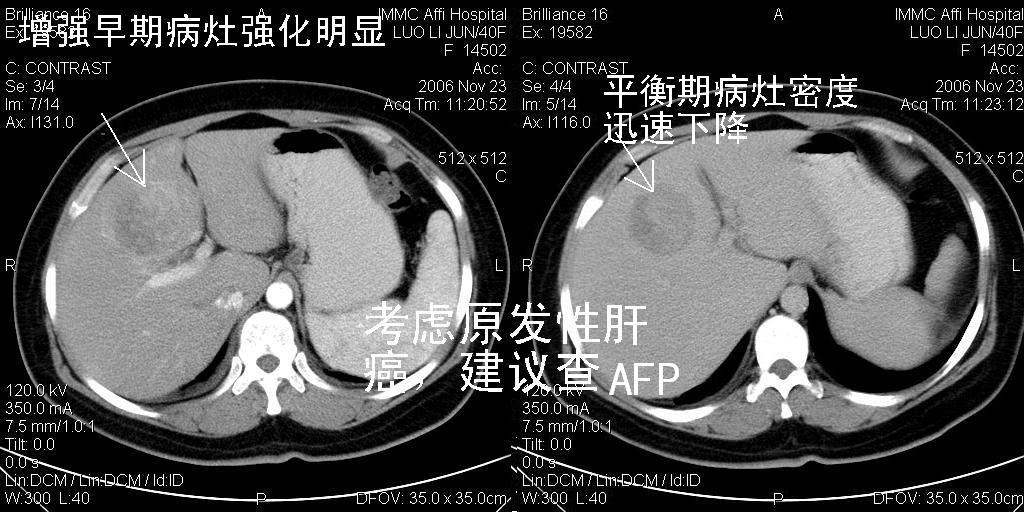

标题: CT5664:我也发一个肝脏的片子大家看看

很典型的肝癌。

速升速降,典型肝癌.

支持-----考虑肝癌----[-从片上看增强早期应该是动脉晚期即门脉早期]

是啊,典型的早出早归!

快进快出典型肝癌.

快进快出,肝癌

符合肝癌的增强特征。支持肝癌!

很好的片子,可惜增强做的比较失败,a期时间没有把我好,实际到了静脉早期了,否则会更典型。

最终考虑是肝腺瘤